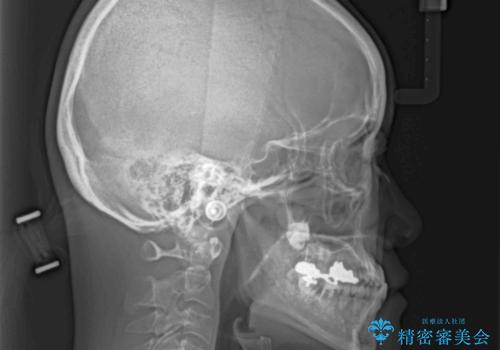

- 前歯の反対咬合により、日々強い痛みを感じているとのことで来院された患者様です。

骨格的に下顎が前方位にありますが、歯列矯正で前歯の被蓋関係を改善することができると判断されたため、インビザラインにより矯正治療を行うこととしました。

また、上顎前歯と下顎大臼歯に神経を取り除いた歯があったため、矯正治療後に、セラミッククラウンにて補綴することとしました。